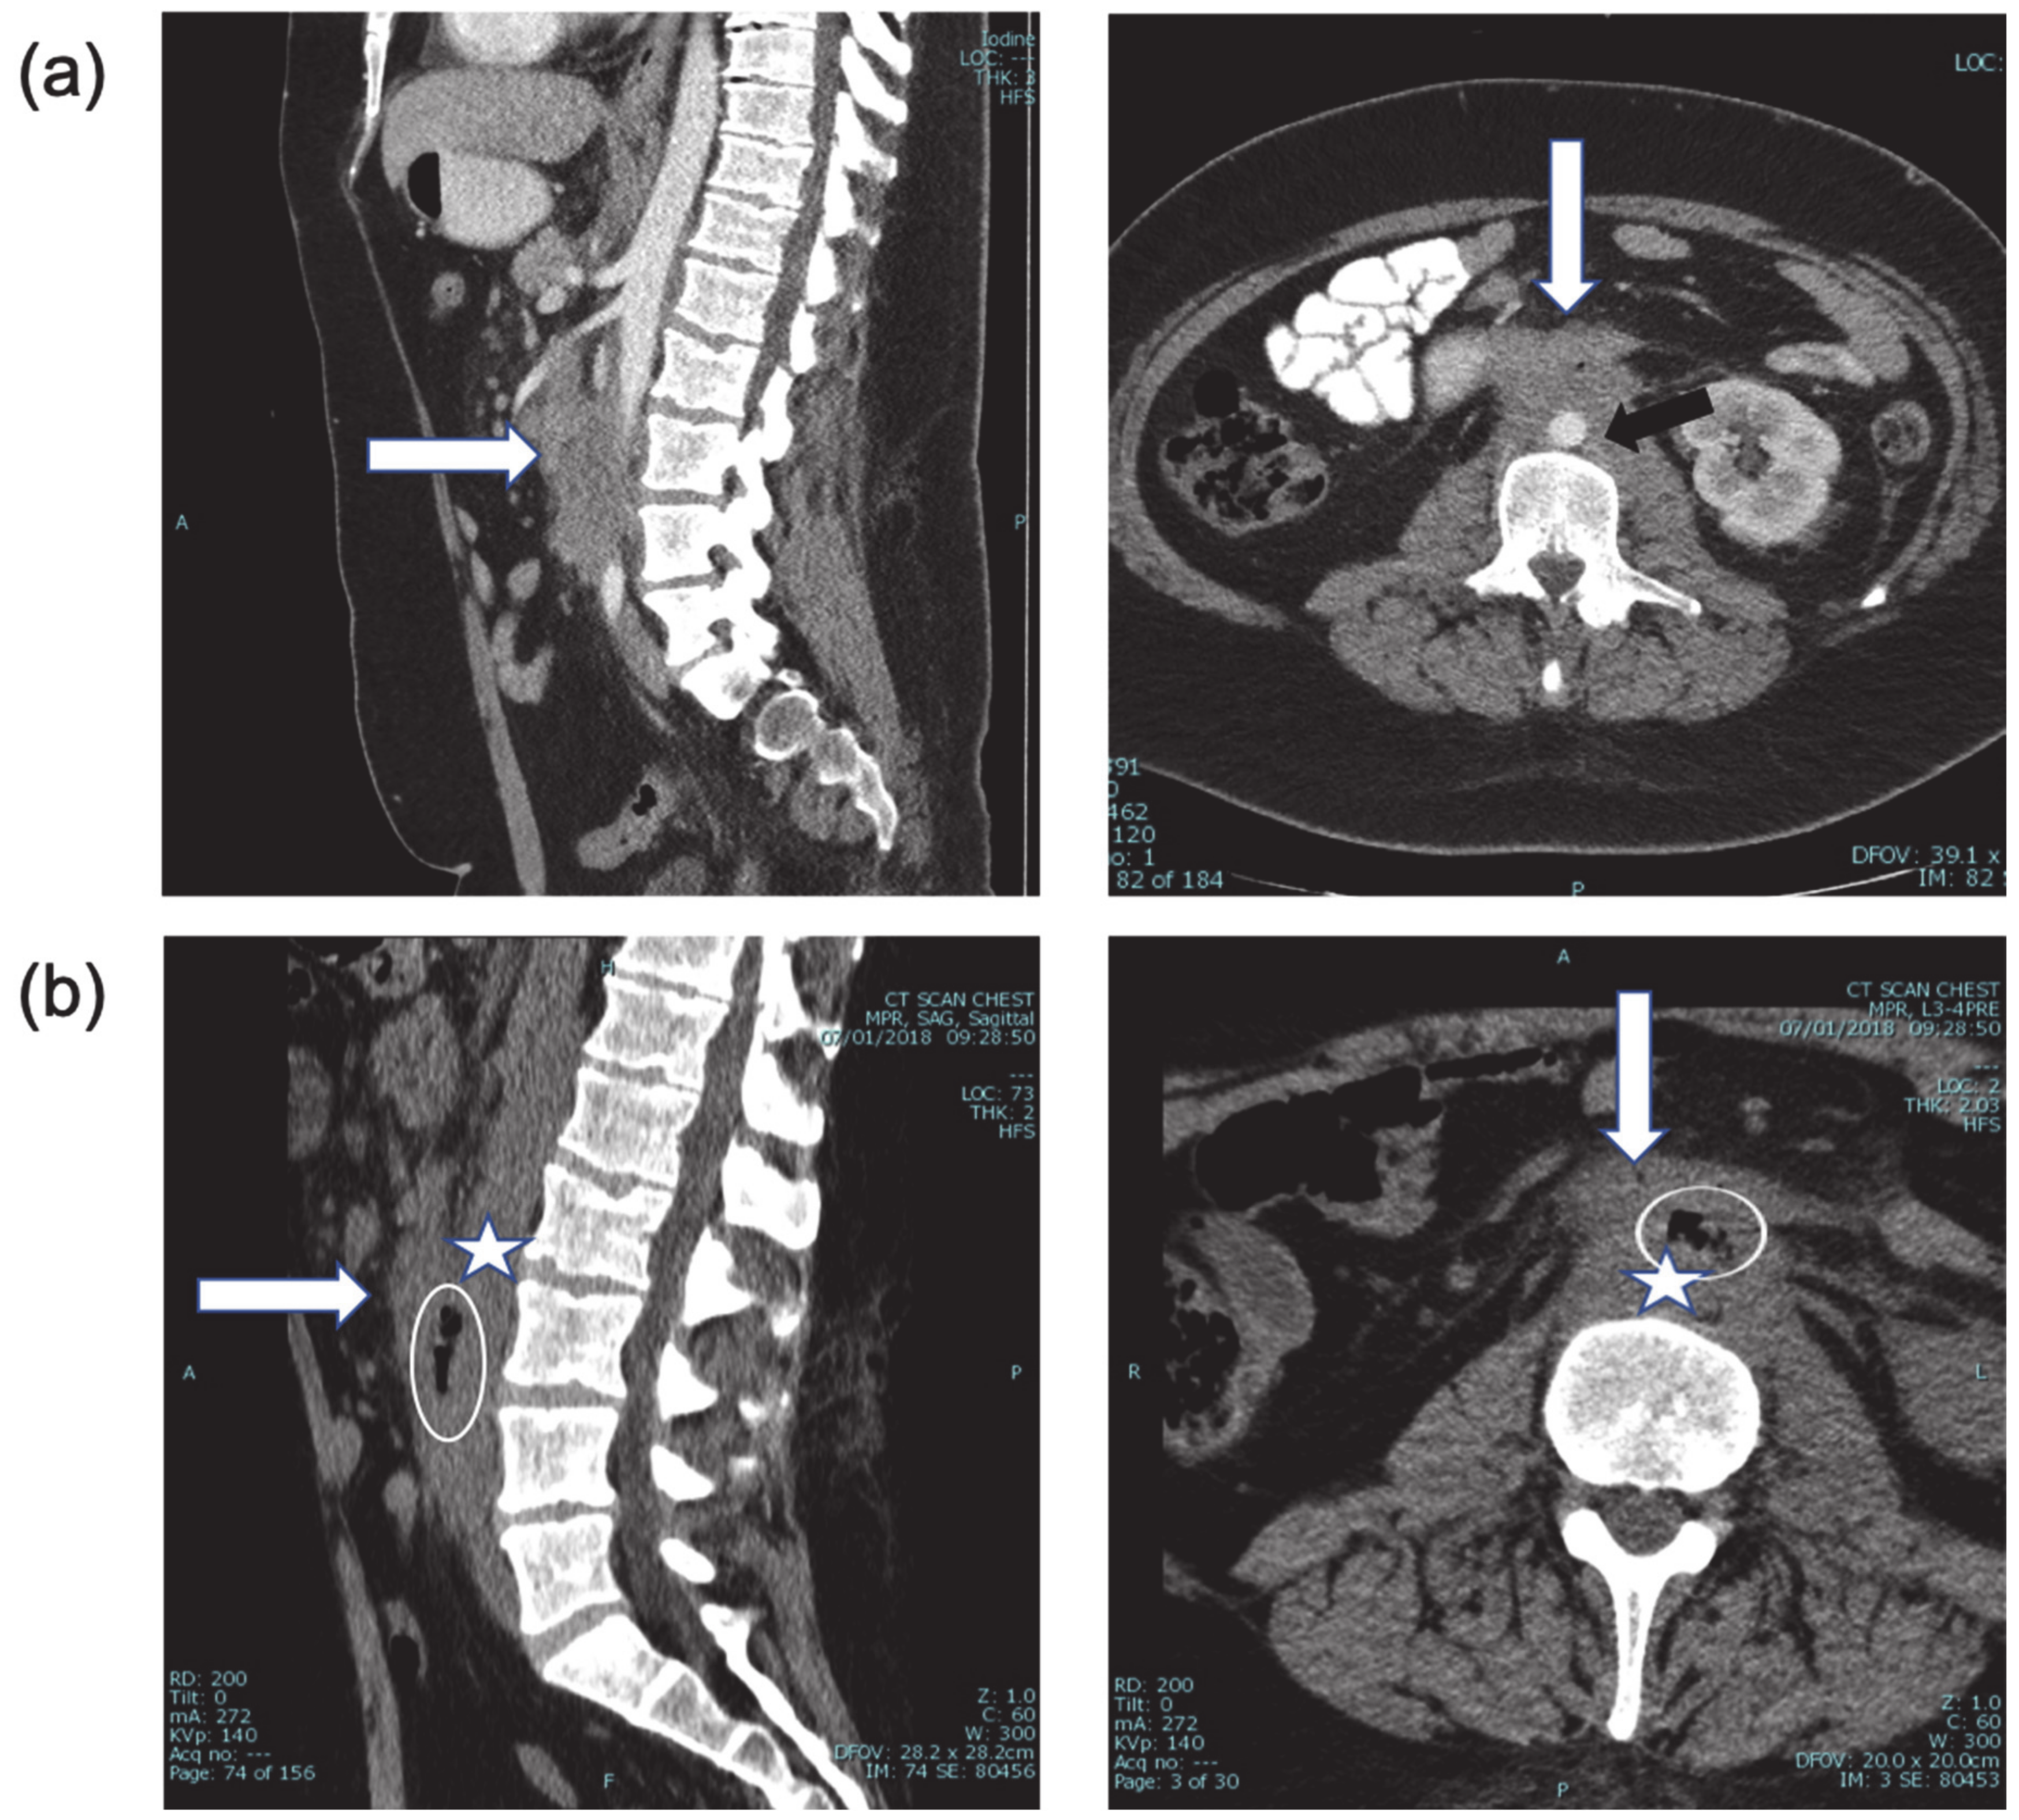

Urgent visceral angiography of celiac, superior mesenteric, left gastric, and gastroduodenal arteries was performed revealing an active source of arterial hemorrhage from a peripheral branch of the left gastric artery in the area of the gastric fundus, managed by selective coil embolization. Despite embolization, severe hematemesis and hematochezia continued, causing persistent hemodynamic instability and prompting the performance of a lateral abdominal aortography, which demonstrated active extravasation of blood into the intestine, diagnostic of an aorto-duodenal fistula (Figure 2a). Temporary balloon occlusion of the aorta was performed to stabilize the patient and control the hemorrhage. The fistula was then closed using a balloon-expandable covered stent (BeGraft, Bentley Innomed GmbH, Hechingen, Germany) at the site of the defect in the aortic wall, with immediate hemodynamic stabilization (Figure 2b). During the entire procedure, the patient received aggressive blood component support to prevent exsanguination, with 27 units of PRBC (Packed Red Blood Cells), 15 units of platelets, 22 units of FFP (Fresh Frozen Plasma) and 20 units of Cryoprecipitate administered over 3 h, in compliance with the institutional massive transfusion protocol (1PRBC:1FFP:1Platlet).

Figure 2. (a) Lateral digital subtraction aortography showing active contrast extravasation from the anterior infra renal aorta into small bowel lumen (arrow)—AEF. Note the diffuse small caliber branch vessels due to vasoconstriction in the setting of hemorrhagic shock. (b) Anterolateral aortogram after covered stent deployment in the infra renal aorta, covering the AEF (arrows). Note that extravasation is no longer seen, and there is some increase in vessel caliber due to improved hemodynamic status.